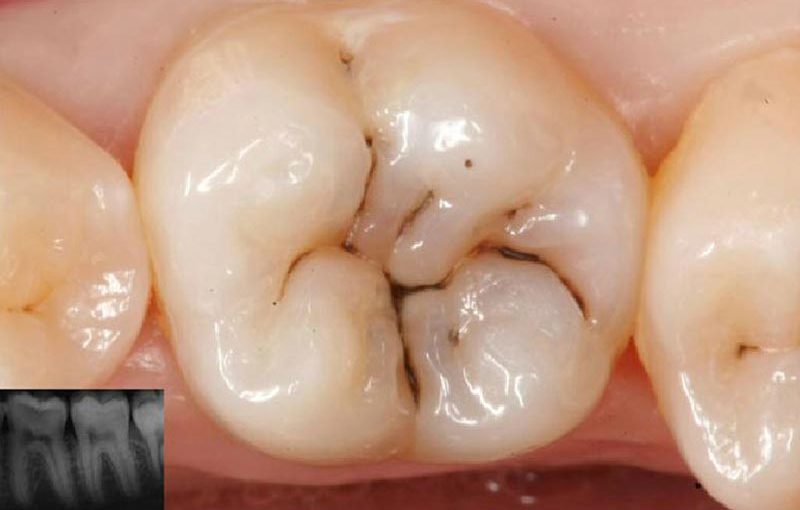

Las caries de la imagen se clasificarían como:

interprox